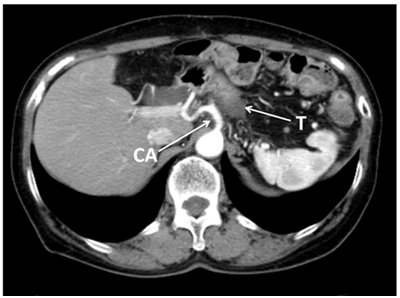

The patients included 5 males and 6 females. Their median age was 76.5(56-86)years. None of the examined patient characteristics, including age; gender; the preoperative serum levels of total bilirubin, AST, ALT, ALP, CRP, and amylase; and the WBC differed significantly between the two groups (Table 1). In addition, there were no significant intergroup differences in the postoperative serum levels of total bilirubin, AST, ALT, ALP, CRP, or amylase or the WBC on POD 1 or 3. In the DP-CAR group, high serum AST, ALT, and ALP levels were detected in one case (Figure 2) on POD 1, but they had decreased by POD 3.

Figure 2 Abdominal CT showed locally advanced cancer of the body of the pancreas. The tumor (T) had infiltrated into the celiac axis (CA), splenic artery (SA), superior mesenteric artery (SMA) and perineural invasion into the surrounding nerve plexus was also observed.